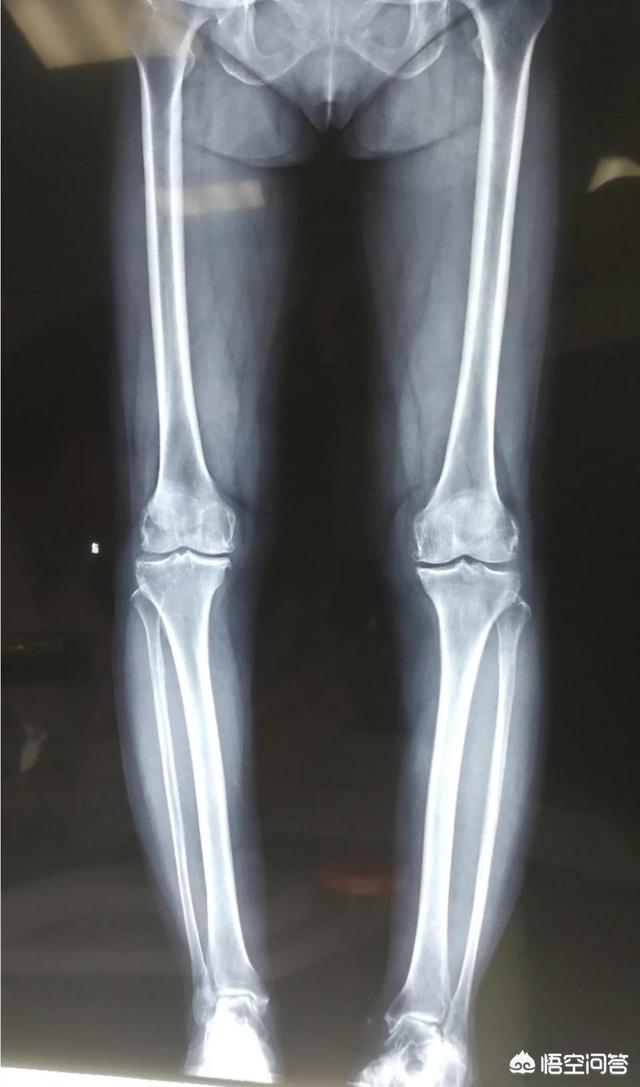

O型腿属于膝关节内翻的范畴。引起O型腿大多数情况下是由于关节结构的发育不良,骨折愈合畸形,退变等因素引起。

通过训练内收肌群而改善O型腿往往是杯水车薪,尤其是对于成年人,且内翻角度较大的畸形。另外,O型腿可由关节外及关节内畸形造成。因此,对于此类患者的治疗需要明确诊断,掌握内翻的角度,适当的时候可以手术矫形。

长期膝关节的内翻畸形不干预,张医生提醒这类病友需要高度警惕!因为不正确的运动+力线的不正常,会促进软骨的磨损及退变,加速膝骨关节炎的进展。